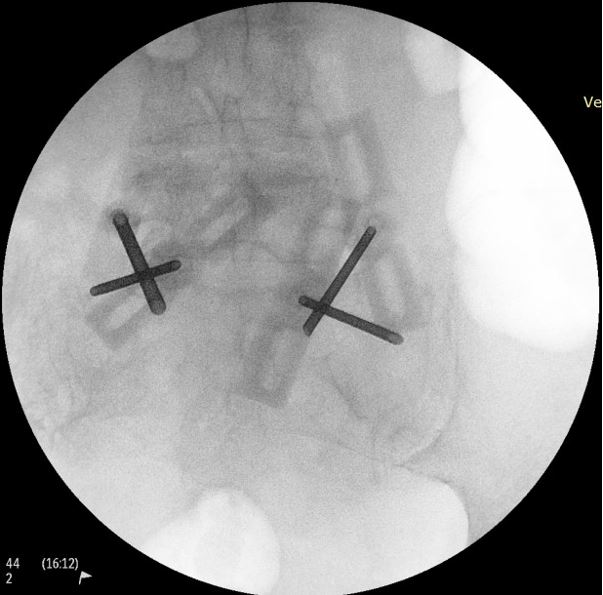

מחדירים ארבעה מחטים תחת שיקוף לעצם העצה, ביניהם מתחבא בלון זעיר המתנפח בעודו במחט, לאחר חדירת המחטים מסירים את הבלון, ובחלל שנוצר במקום הבלון מחדירם צמנט אורתופדי, המתקשה במהירות וככה הוא מייצב את עצם העצה ומפחית ברמה משמעותית את הכאבים.